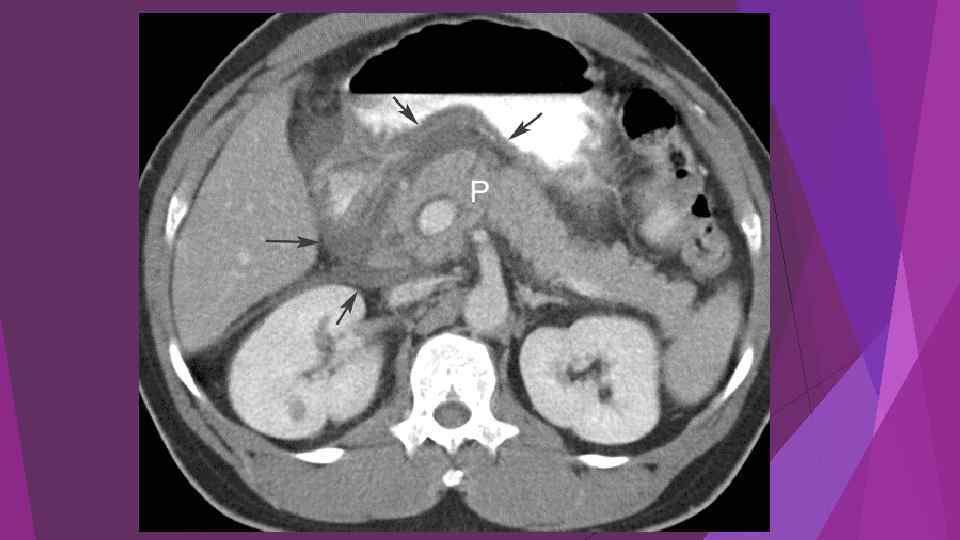

Острый панкреатит, деструктивная форма. Увеличение размеров

Острый панкреатит, деструктивная форма. Увеличение размеров

Diagnosis and differential diagnosis of acute pancreatitis are as follows: Accordi ng to the typical clinical manifestations and laboratory tests, can often make the diagnosis. Patients with mild persistent and severe abdominal pain, nausea, vomiting,

Diagnosis and differential diagnosis of acute pancreatitis are as follows: Accordi ng to the typical clinical manifestations and laboratory tests, can often make the diagnosis. Patients with mild persistent and severe abdominal pain, nausea, vomiting,